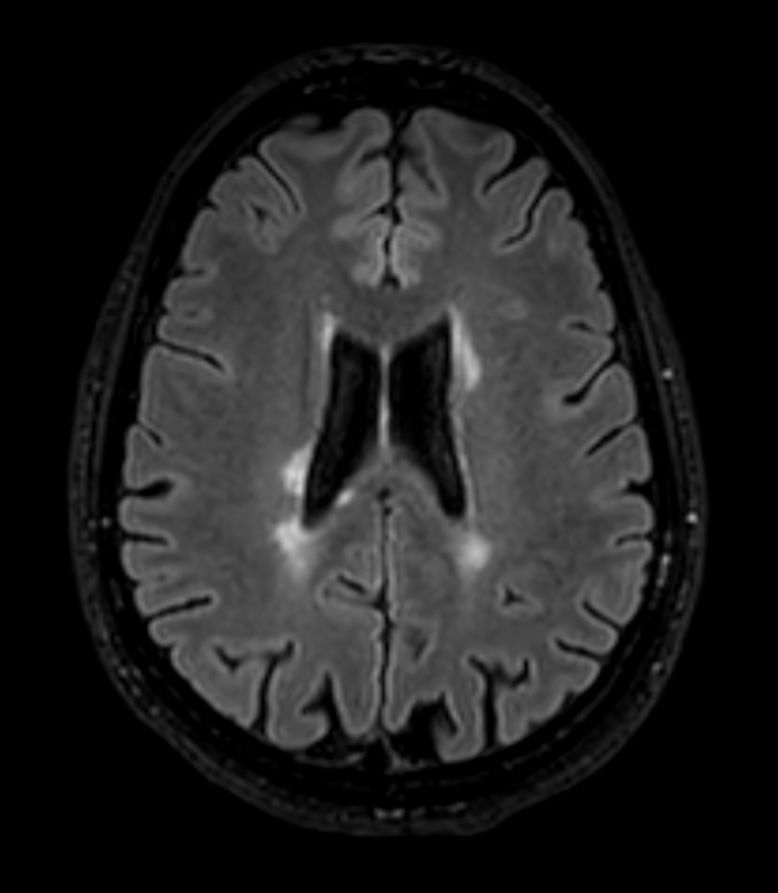

DWI b1000

3D T2w FLAIR BrainVIEW Compressed SENSE

3D T2w FLAIR BrainVIEW (reformat) Compressed SENSE